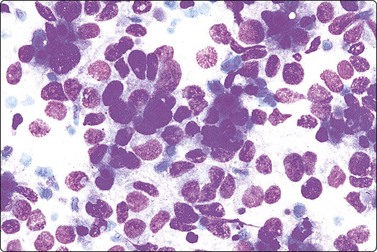

Seminoma (Figs 13.30 and 13.31)14,50,57-63,65,66

image image

Fig. 13.30 Seminoma

(A) Dispersed cells with large pale nuclei and poorly defined cytoplasm; note ‘tigroid’ background, smudged nuclei and small lymphocytes (MGG, HP); (B) Dispersed cells; moderately pleomorphic vesicular nuclei; single or multiple prominent nucleoli; many scattered lymphocytes (Pap, HP).

image

Criteria for diagnosis

Cell-rich smears,

Dispersed cells, little tendency to clustering,

Highly fragile cytoplasm and nuclei (’tigroid background’ (TB) and nuclear trailing),

Large rounded vesicular nuclei; distinct nucleoli, smaller than in embryonal carcinoma,

Irregular chromatin with some clearing,

Abundant fragile, pale/clear cytoplasm; some marginal vacuoles (punched-out vacuoles),

Lymphocytes, plasma cells,

Tangled chromatin threads (seminoma cells and lymphocytes),

Some epithelioid histiocytes, epithelioid granulomas (variable),

Striking contrast in size between seminoma cells and the background of lymphocytes and plasma cells.

Immunocytochemistry: cells positive for PLAP, c-kit (CD117) and OCT 3/4, and negative for CD30, AE1/AE3, and CK7, CK8, CK18 and CK19, although focal pancytokeratin-positive cells may be seen.

Seminoma is a highly cellular neoplasm of poorly cohesive cells and little stroma. The presence of a lace-like tigroid background (TB), and the high cellularity including lymphocytes account for the intense navy-blue color of the smears. This may suggest the diagnosis even before microscopic study. Comments about the origin of TB and the distinction from ‘lymphoglandular bodies’ have been made elsewhere.60 TB may go unnoticed in Pap-stained smears, but is more conspicuous in DQ smears (Fig. 13.30). A diagnosis of seminoma should not be based solely on the presence of TB or TB-like material. We have observed TB-like material also in aspirates of embryonal carcinoma. The contrary is also true: seminoma should not be ruled out simply because the pathologist is unable to identify TB.14 Large seminomas may show prominent necrosis. Necrosis is a major cause of false negatives in testicular FNA.59 Tumor giant cells or syncytiotrophoblastic cells may be seen in aspirates of seminoma, but can also be found in embryonal carcinoma, mixed TGCT and in trophoblastic tumors.

The plasmatic membrane is well-defined in seminoma, but it is difficult to see in embryonal carcinoma. When lymphocytes, plasma cells, histiocytes and epithelioid granulomas are abundant and seminoma cells scarce, a diagnosis of granulomatous orchitis may be entertained: the absence of spermatozoids and of the germinal line suggest a seminoma.60

Chromatin trailing may be prominent, particularly if the sample was smeared vigorously. This artifact has no diagnostic value in itself, since it may occur also in embryonal carcinoma, yolk sac tumors, lymphomas and acute orchitis. When the smear is dominated by this artifact, and there are no acute inflammatory cells and no spermatogenesis, the pathologist must search carefully for preserved diagnostic cells. In this situation, a tentative diagnosis of seminoma may be made.14

Lymphocytes, plasma cells and even ‘lymphoglandular bodies’ may be prominent in smears of seminoma and may lead to an erroneous diagnosis of lymphoma. Lymphoblasts may also be mistaken for seminoma cells.

Familiarity with the cytology of testicular seminoma helps in the recognition of extragonadal seminoma and metastatic seminomas (Fig. 13.31). Immunostaining may be of help in doubtful cases.69

Seminomas with a greater degree of cellular pleomorphism, higher mitotic rate and scarce stromal lymphocytes have been called anaplastic seminoma or atypical seminoma.12 These seminomas may be mistaken for embryonal carcinoma.65